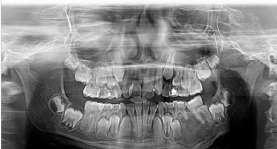

Melinda och Elisabeth har gjort sitt examensarbete tillsammans inom endodonti.

– Vi tittade på patientfall som fått kronterapi och hur tandpulpan reagerat, säger Melinda

De ville veta om patienterna fått genomgå ett pulpa-

test – olika faktorer mäts som kan påverka pulpans överlevnad vid kronterapi.

Det är bra att förbättra rutinerna på det här området, därför har vi tagit fram ett förslag så att inget missas, säger Elisabeth